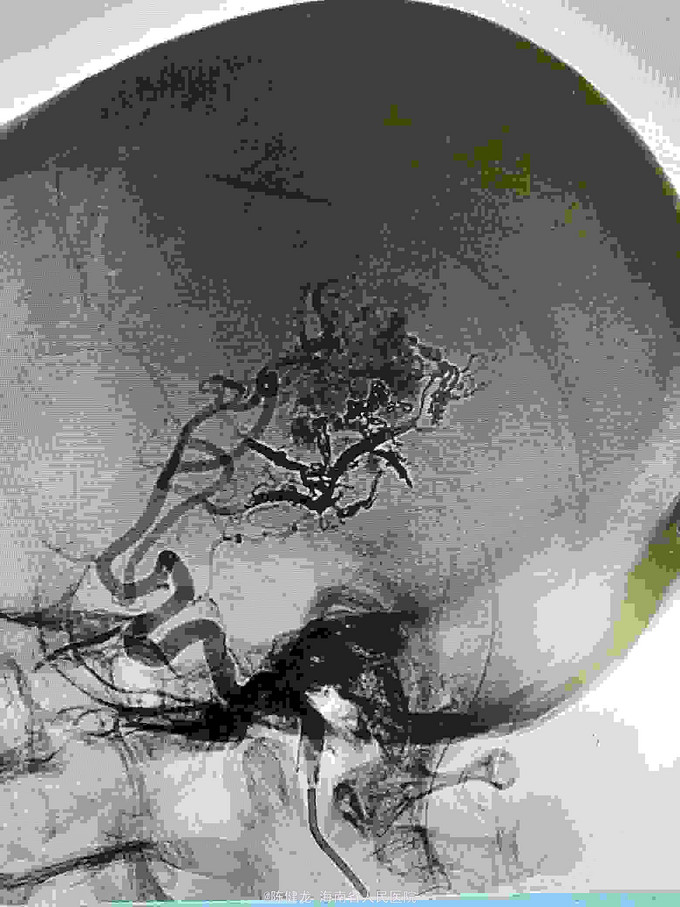

AVM

右颞大型AVM,大脑中主要供血。

右颞AVM

己进行二次治疗,拟近期内进行第三次治疗。争取80%至90%栓塞,残留部分伽玛刀治疗。